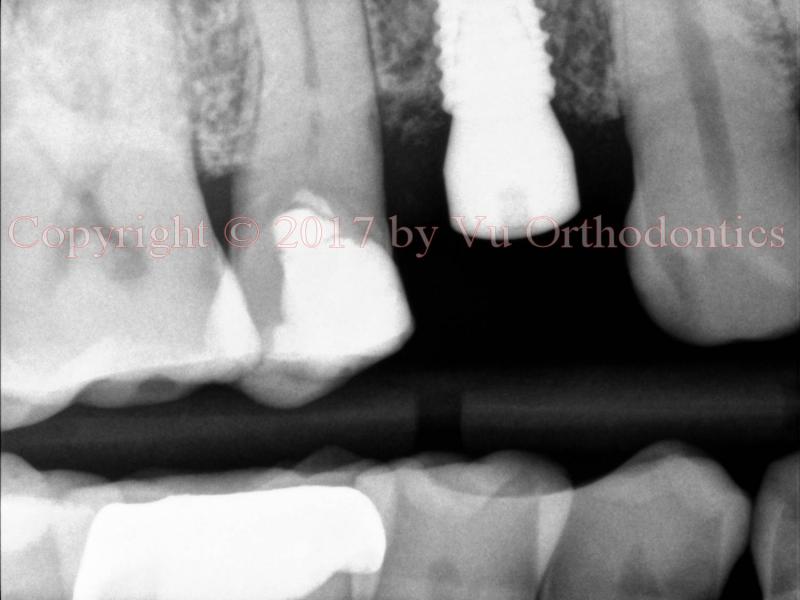

A case of bad implant placement (which was done elsewhere) is shown in Fig. 1. In this case, the implant was placed not parallel to the adjacent roots. Its axis should be along the yellow line -- not the red one. It was also placed too deep. More importantly, the implant is of the wrong type. It is a tissue-level implant (of Straumann), so the top part of the implant should be above the bone level -- should not be below the bone level, as shown.

Fig. 1. Bad implant placement: the axis is supposed to follow the yellow line, not the red one.